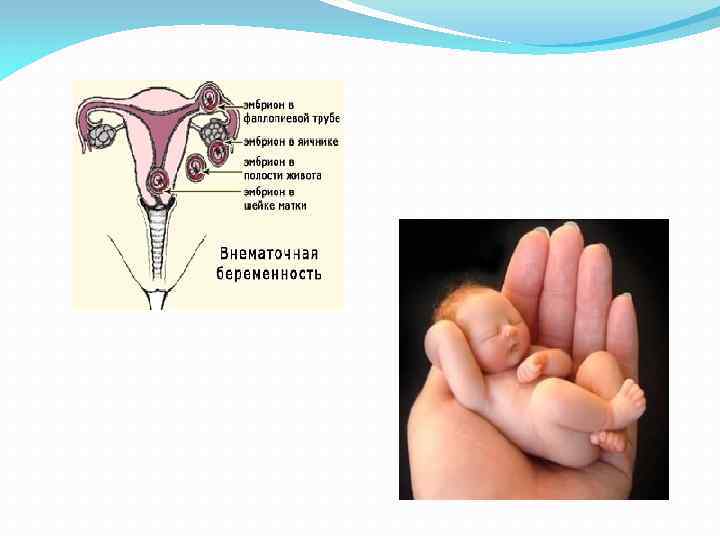

Заблуждения и факты о внутрибрюшной беременности